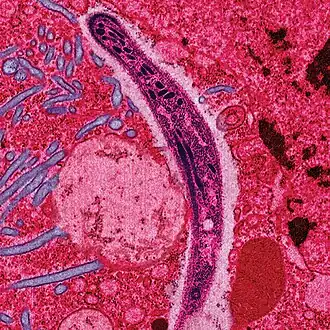

- meercellige parasieten, zoals spoelwormen, lintwormen en schurftmijten

Een infectie ontstaat als een pathogeen invasief wordt, het bloed of weefsels binnendringt. Een toxi-infectie is een infectie waarbij de pathogenen giftige stoffen afscheiden, zelfs als de pathogenen zelf niet in het lichaam binnendringen. Voorbeeld: wanneer een gewone huidbacterie op een plek in het lichaam wordt gebracht die normaal steriel is, kan die daar ongebreideld groeien en een enorme last voor de gastheer veroorzaken. Voorbeeld: puistjes, de Staphylococcus aureus veroorzaakt een hevige haarfollikel-infectie.